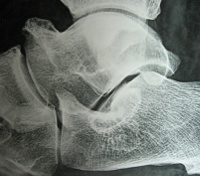

Ακτινολογικά σχεδόν πάντα υπάρχουν ευρήματα όπως:

1. Οστικές γέφυρες του ταρσού,

2. Κατάγματα της περιοχής,

3. Κάθετη θέση του αστραγάλου.